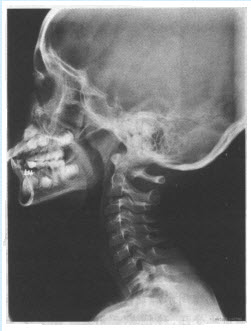

患儿,男,5岁。反复呛咳,张口呼吸,有鼾声,鼻腔分泌物多。X线检查如图所见。最可能的诊断是()

A:鼻窦炎

B:鼻息肉

C:扁桃体炎

D:腺样体肥大

E:鼻炎